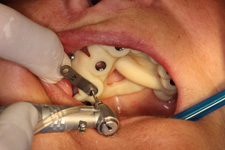

Principem řízené navigace pomocí chirurgických šablon je pasivní vedení zahlubovacích a rozšiřovacích vrtáčků do čelistní kosti na základě předem naplánované přesné pozice, směru, sklonu a hloubce jednoho nebo více implantátů. Chirurgicko-protetický plán vychází z 3D rentgenu čelisti, otisku zubů a dásně (scanu zubů a dásně) a finálního návrhu protetické náhrady. Na základě těchto dat je v plánovacím softwaru coDiagnostiX vytvořena chirurgická šablona, která je následně vytištěna na 3D tiskárně a použitá v den výkonu. Od roku 2014 jsme tuto metodu jako první v ČR začali využívat a nadále se podílíme na vývoji a vylepšování chirurgických šablon pro ještě přesnější a předvídatelnější výsledky.

7) Operace pomocí šablony